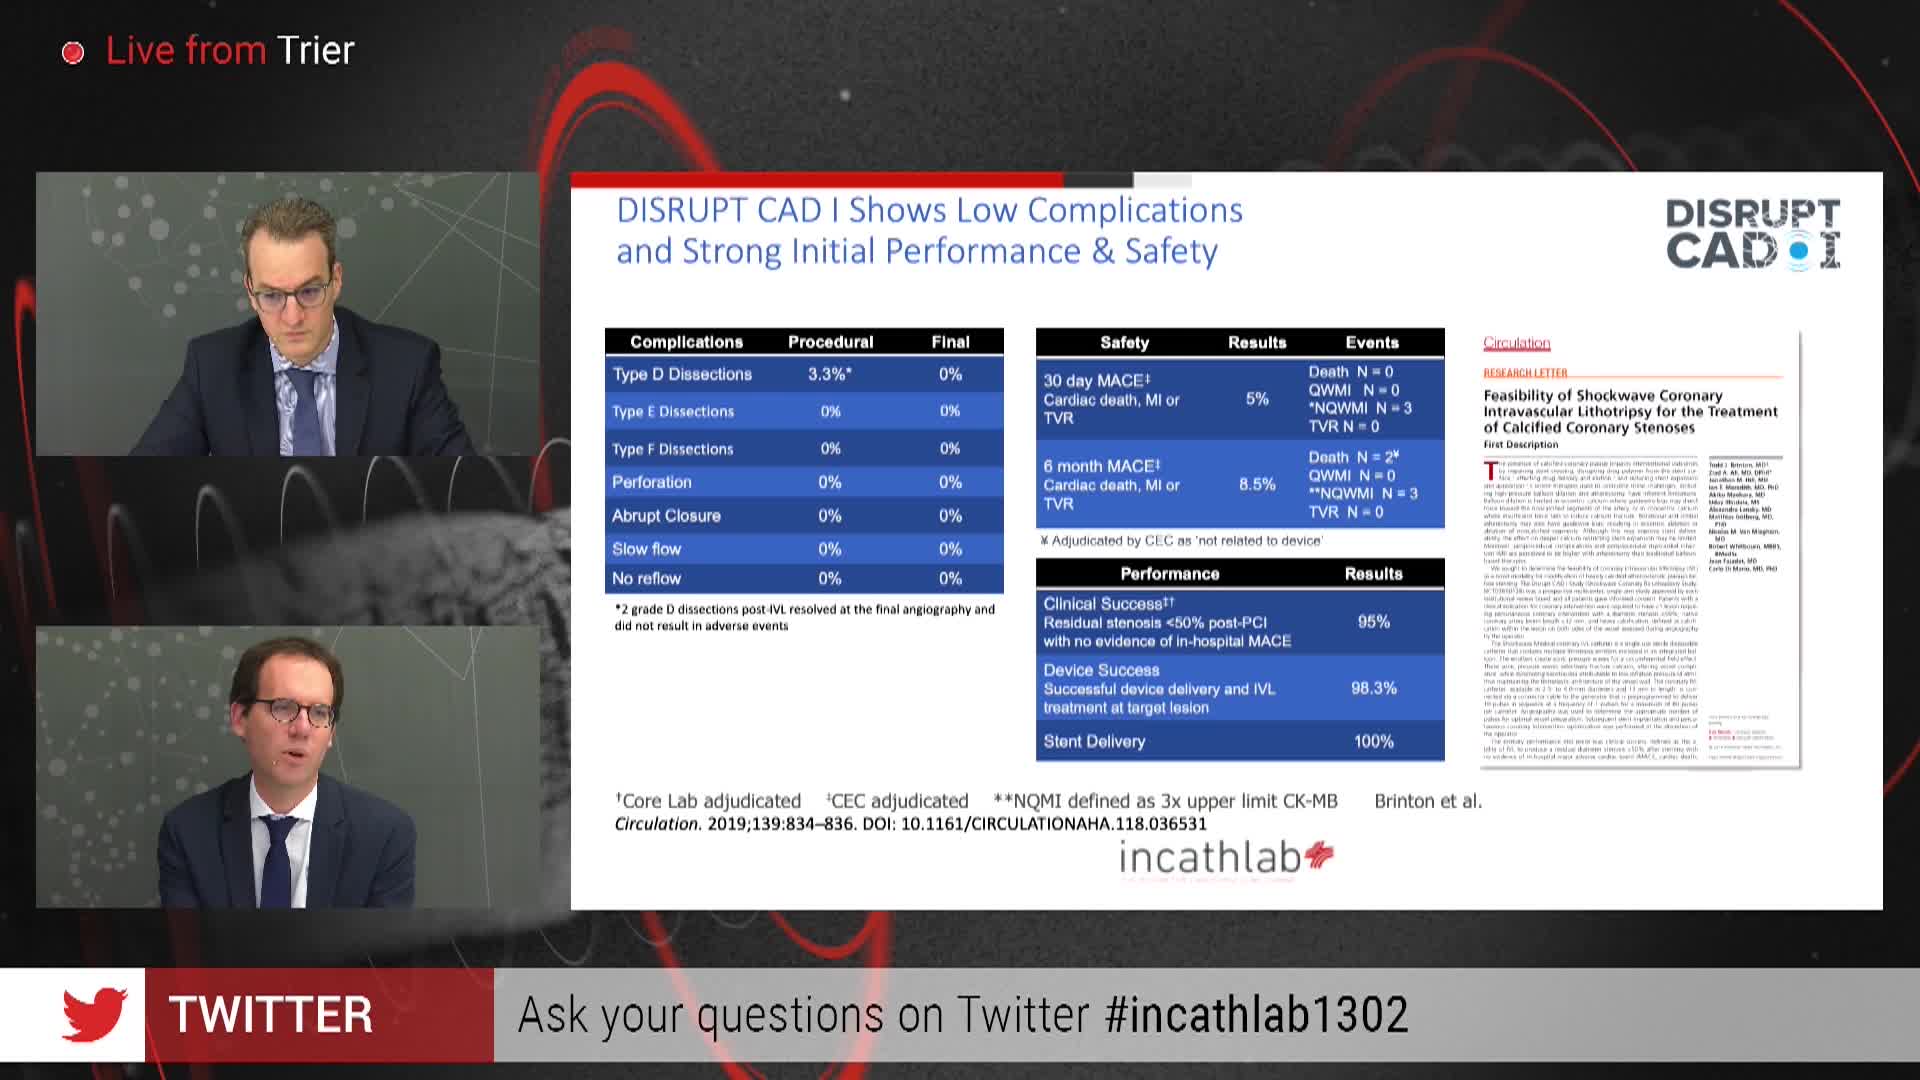

Shockwave IVL Coronary Real-World Cases, Outcomes & Algorithms: An InCathLab Webinar